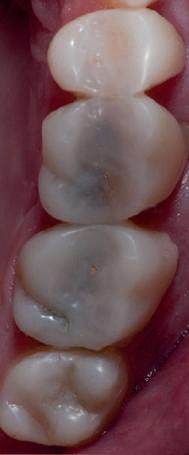

Atitudine: Până la dobândirea vindecării totale a ţesuturilor şi a implanturilor secundare s-au utilizat bonturi standard de titan. Fig. 18 prezintă bonturile individualizate maxilare şi mandibulare aplicate iar fig. 19 un prim-plan al cadranelor de partea dreaptă a pacientului, afişând finalizarea cazului la 15 luni după începerea tratamentului iniţial. Recesiile se pot obiectiva corespunzător 1.4. şi 1.3. În acest caz, s-a încercat minimizarea susceptibilităţii la recesie prin implicarea bonturilor temporare standard fixate cu şurub în cursul fazelor de vindecare pe toată durata etapelor iniţiale ale tratamentului.

Rezultatul final al cazului 5 (fig. 19) prezintă recesie vestibulară de peste 2mm în jurul bonturilor cu sprijin implantar, fiind evidentă prezenţa unui ţesut moale foarte redus din cauza plasării vestibulare a implanturilor. Butler, Kinzer susţin premiza că trebuie să existe suficient volum osos vestibular, chiar şi atunci când implantul este plasat ideal, multe complicaţii fiind legate mai degrabă de poziţia implantului.

Cazul (5):

Bonturi conice utilizate ca bonturi temporare

Figurile

16, 17. Implanturile din prima etapă încărcate cu bonturi conice şi, în unele cazuri, omologii angulaţi.

18. Bonturile individualizate inserate.

19. Rezultat final la 15 luni după începerea tratamentului iniţial.

şi va induce resorbţie osoasă şi migraţia apicală a ţesutului (Saadoun & Touati). Dacă implantul nu este plasat mai palatinal şi la 3-4mm apical de marginea gingivală liberă pentru a asigura profilul de emergenţă adecvat, rezultatul estetic este compromis (Chu et al). Un studiu de 2 ani a demonstrat că implanturile poziţionate anterior au demonstrat o recesie uşor mai accentuată, decât implanturile posterioare (Bengazi et al). Plasarea vestibulară a implanturilor se poate vizualiza clar în cazul 5 (fig. 17) cu bonturile de vindecare în poziţie.